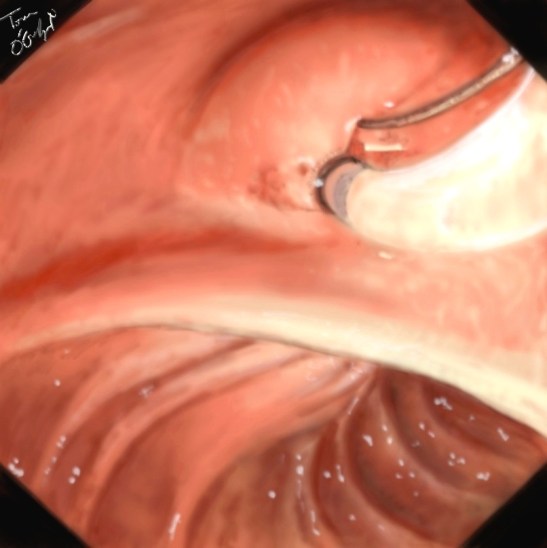

spinctérotomie endoscopique CPRE

sphinctérotomie endoscopique, section de la papille

Cholangiopancréatographie rétrograde endoscopique CPRE et drainage biliaire percutané trans hépatique